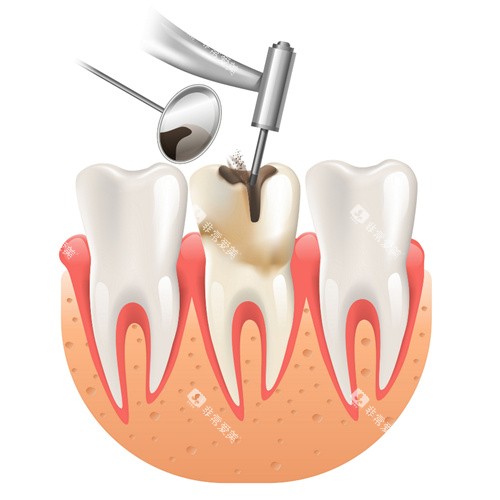

根管治疗的过程

根管治疗是治疗牙髓炎、根尖周炎等牙髓疾病的有效方法。

它主要包括根管预备、根管消毒和根管充填三个步骤。

医生会先去除感染的牙髓组织,然后对根管进行清理、消毒,然后用充填材料将根管填满。

自贡根管治疗价格

在自贡,根管治疗的价格与牙齿的部位有关。

前牙的根管治疗相对简单,费用一般在300 - 500元左右;前磨牙的根管治疗费用大约在500 - 800元;磨牙的根管治疗较为复杂,价格在800 - 1500元之间。